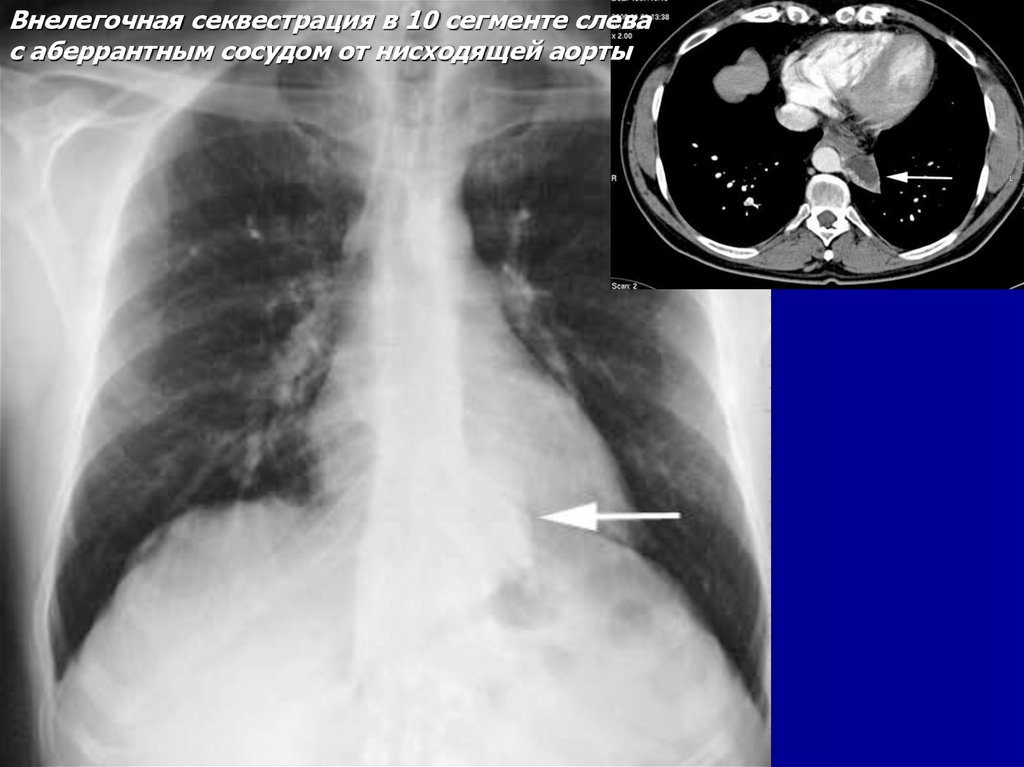

Внелегочная секвестрация

с аберрантным сосудом от нисходящей аорты